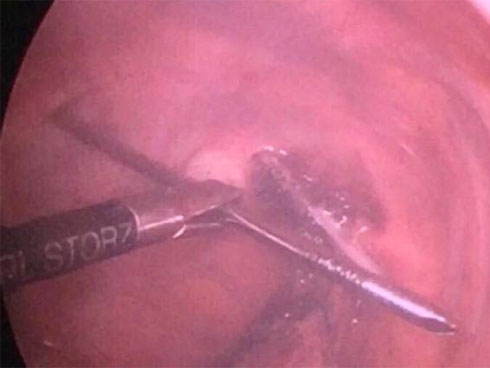

Hai cây đinh được phẫu thuật lấy ra. Ảnh: Bệnh viện cung cấp

Qua thăm khám và làm các cận lâm sàng, như: X-quang ngực, CT-Scan, nội soi thực quản, bệnh nhân được chẩn đoán xác định dị vật vùng cổ do đinh kirschner kết hợp xương đòn đâm xuyên thực quản và khí quản. Ê-kíp bác sĩ đã phẫu thuật lấy đinh và khâu lại thực quản, khí quản cho anh P. Hiện, sức khỏe bệnh nhân ổn định, đã ăn được, dự kiến xuất viện trong vài ngày tới.